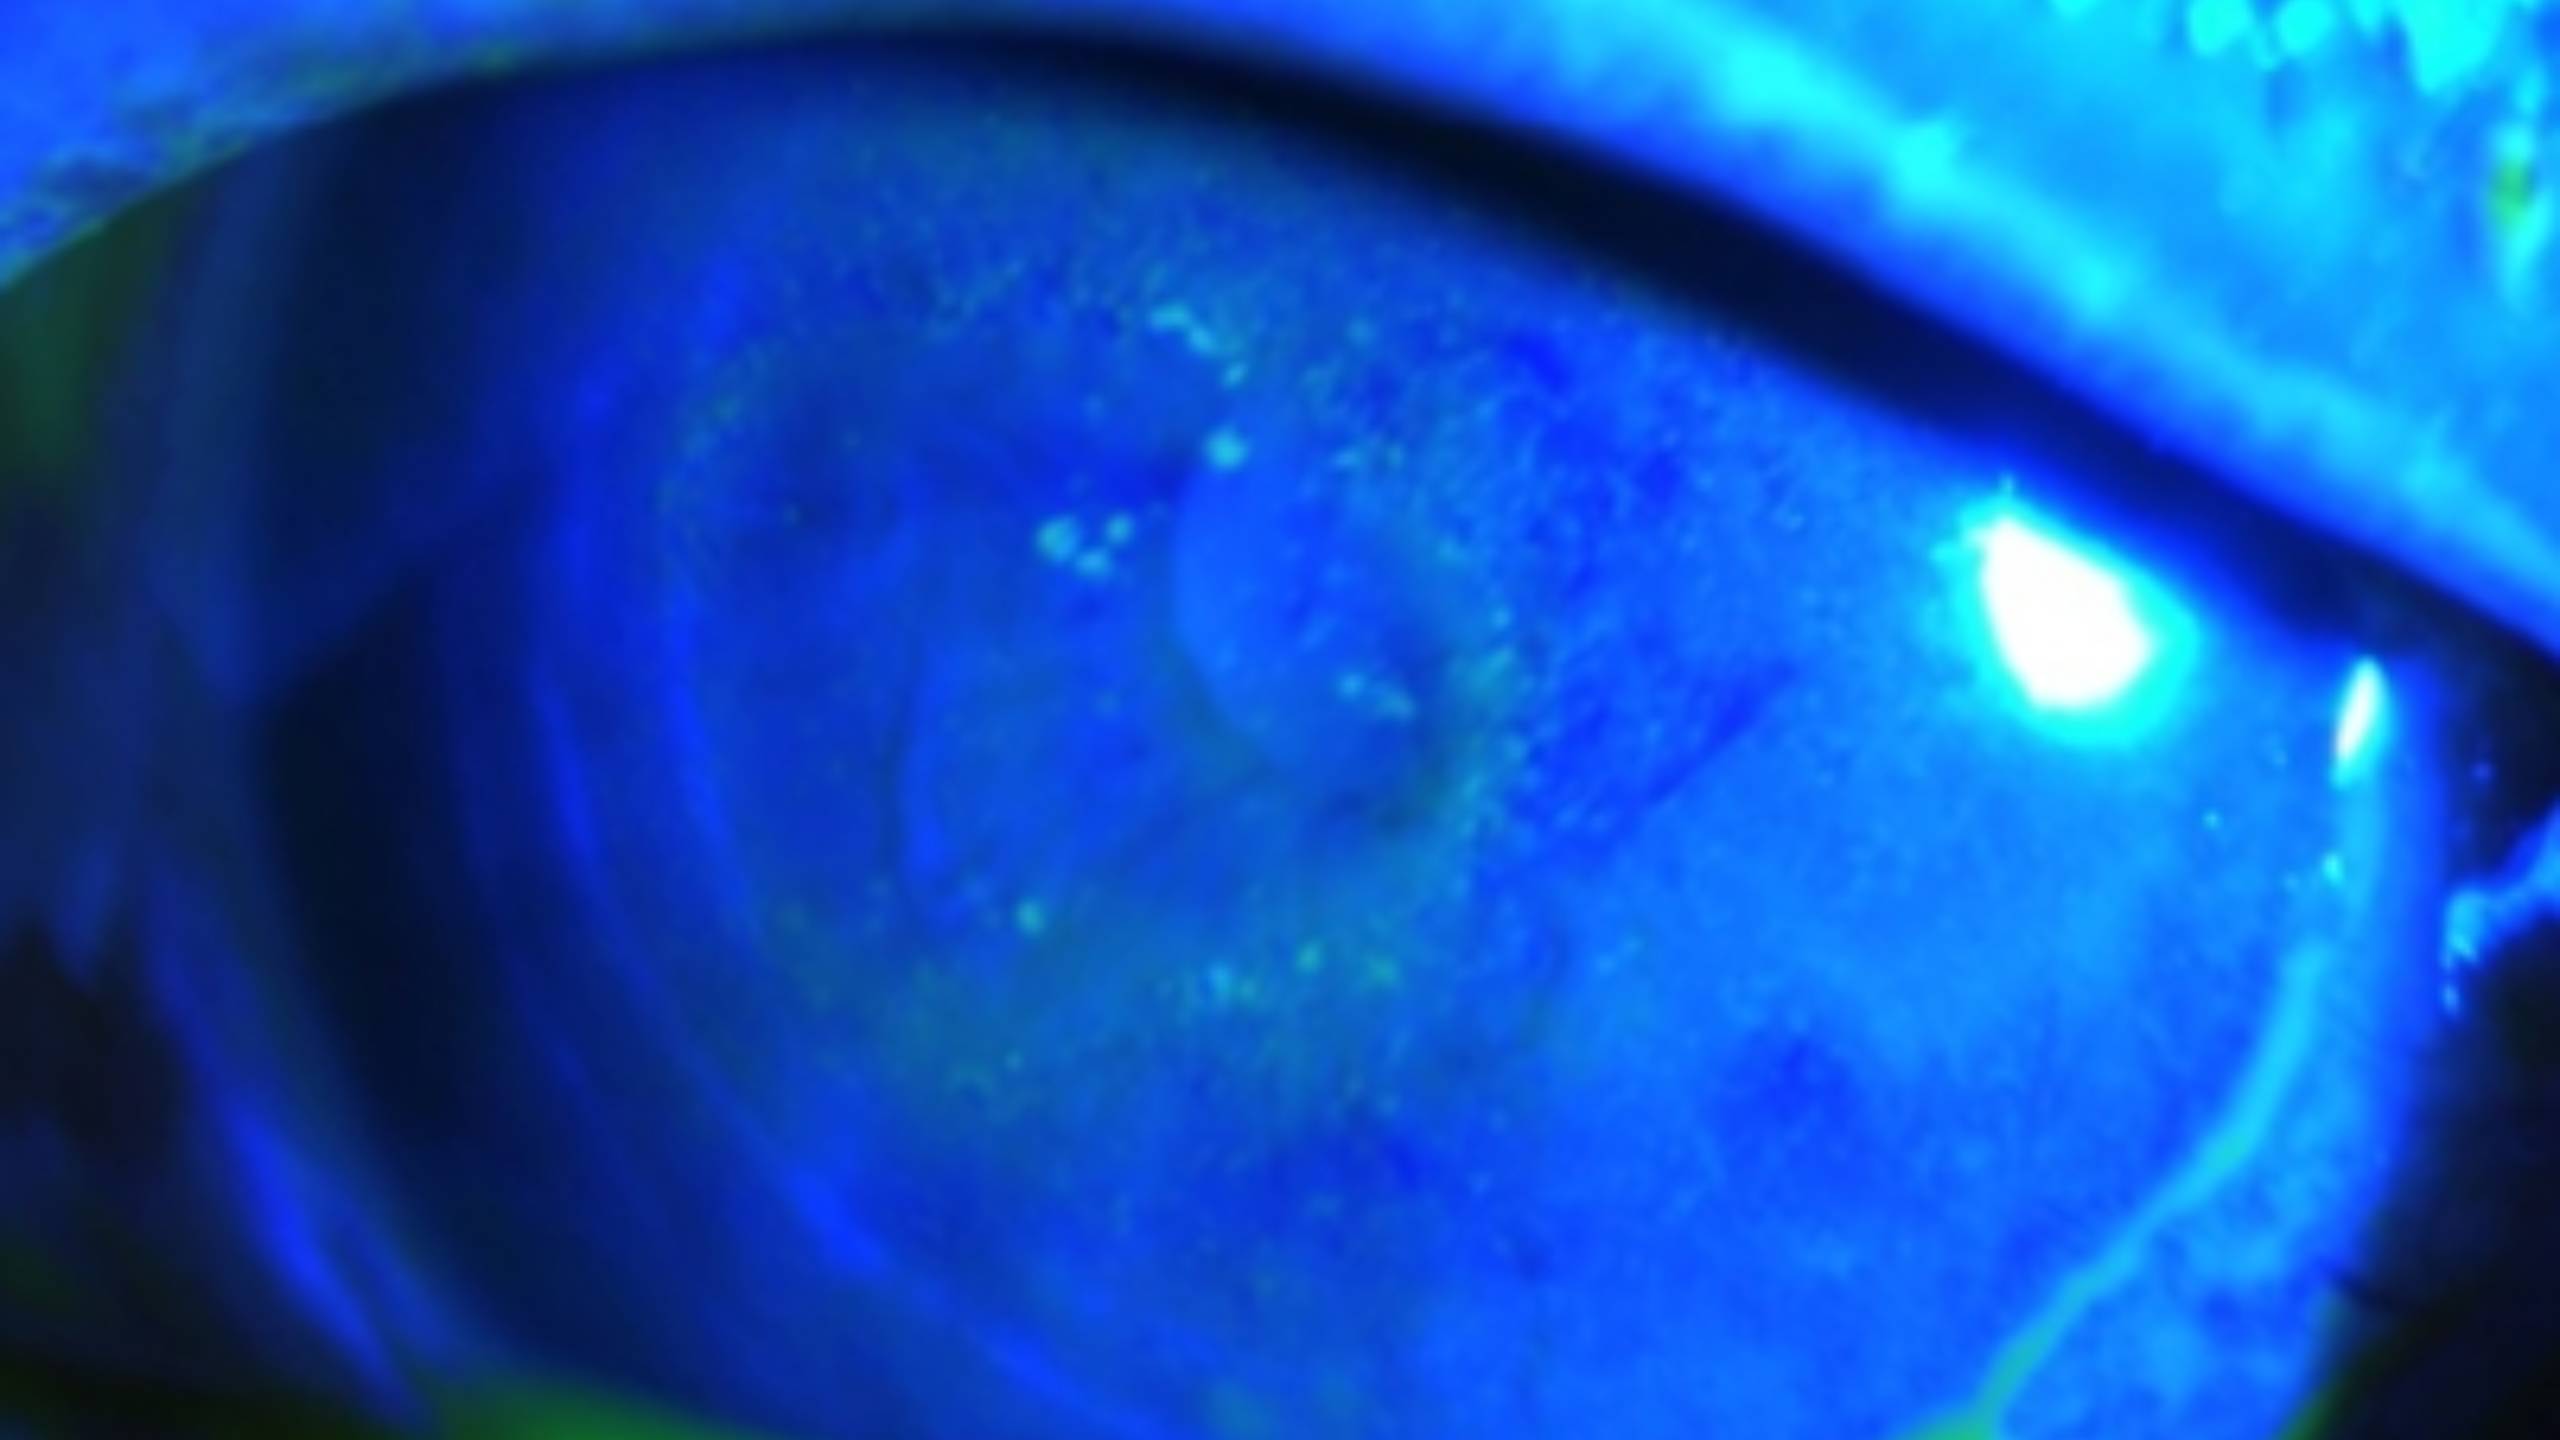

表皮型的症狀包括異物感、眼紅、畏光、視力減退、流淚、眼皮水腫等非特異症狀,可能有前房反應,通常是單眼,但也可能雙眼發生。表皮會有多個邊緣模糊點狀隆起,大小不一、形狀各異的病灶(圖一)。感覺是異物黏在角膜表面,以螢光染色後程度不一(圖二)。乍看之下不會覺得那是感染,而是角膜表皮沾染了什麼東西。用棉棒輕拭也可以去掉,因此更會愚弄醫師,覺得那根本不是感染;但拭除這些小白點後,第二天又在不同位置產生一樣的病灶。

(圖二)以螢光染色後程度不一的異物感